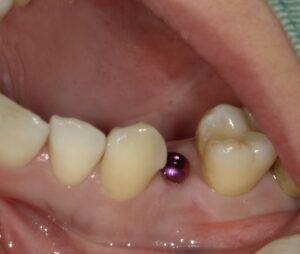

この場合は、外側内側の骨は十分ありましたのでフラップレスと

いい歯肉を切開しない方法でソケットリフトができました。

そのため縫合も必要ありません。